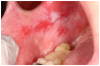

Salivary gland dysfunction and xerostomia associated with cGVHD mimic the clinical features and symptoms of Sjögren syndrome. Hyposalivation impairs the protective activity of saliva, elevating the risk for dental caries and accelerating the progression of white spot lesions, and in some cases, to rampant dental caries and subsequent tooth loss31,40,41 (Figure 2c). Hyposalivation also reduces oral lubrication, which can lead to difficulty speaking, eating, and dysphagia.42 Furthermore, the reduction of salivary proteins (e.g., histatin, lactoferrin, calprotectin) can diminish antimicrobial and antifungal activity, thereby increasing the risk for recurrent oral candidiasis.30,31,43 Oral candidiasis most frequently presents as white pseudomembranous patches but may also present with diffuse erythema (Figure 2d).

Figure 2c. Hyposalivation and dental caries

Figure 2c

Figure 2d. Oral candidiasis

Figure 2d